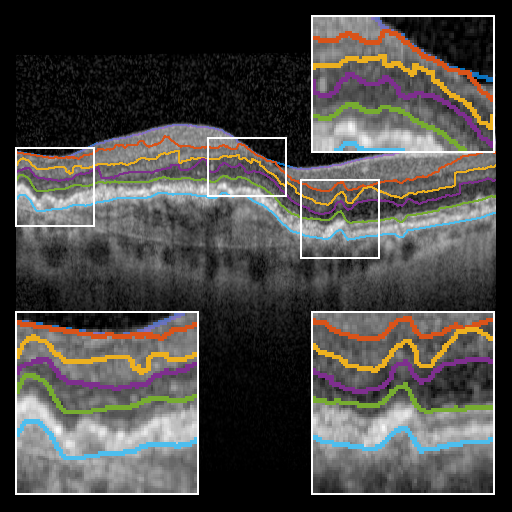

Refer to caption

Figure 3: Qualitative comparison of each segmentation approach. Top row, left to right: ground truth, BRU-net, U-net; bottom row, left-to-right: Dufour et al., Chen et al., Mayer et al. Only BRU-net is able to segment the BM layer under the pathological region. The smaller receptive field of U-net results in discontinuities. Further qualitative results are provided in the supplementary material.

To evaluate BRU-net, we compare it with the 3D methods of Dufour [5], Chen et. al. [4], and the 2D method of Mayer et. al. [12] on the same dataset. Additionally, we train a traditional U-net configuration [14] using the procedure described above. Fig. 3 provides a qualitative comparison of the results.